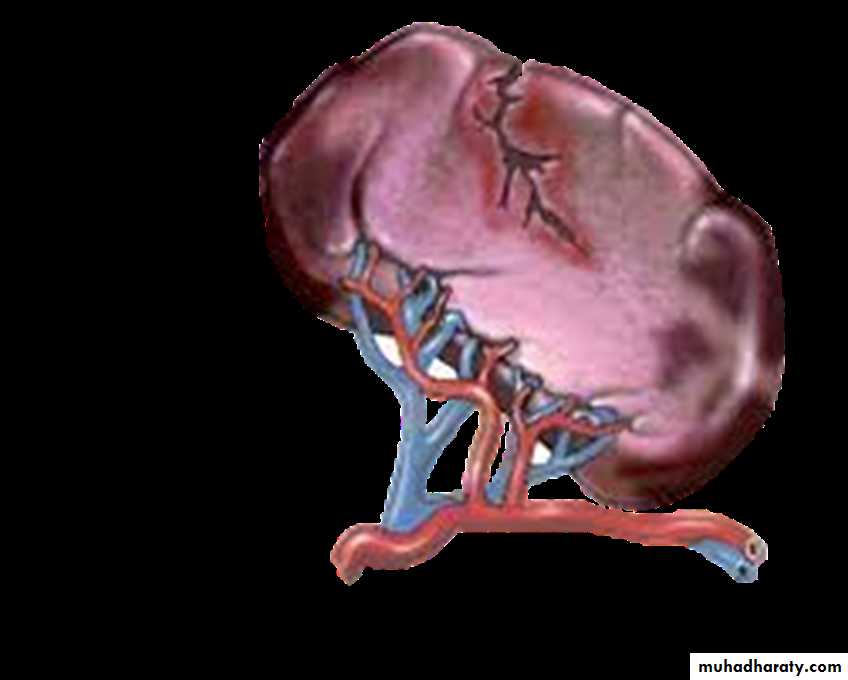

anatomyThe spleen is situated in the left upper quadrant tucked under and against the left dome of the diaphragm and overlain by the lower left 9th to 11th ribs.

They are located near the hilum of the spleen in 50% of cases and are related to the splenic vessels or behind the tail of the pancreas in 30%.

The remainder are located in the mesocolon or the splenic ligaments.